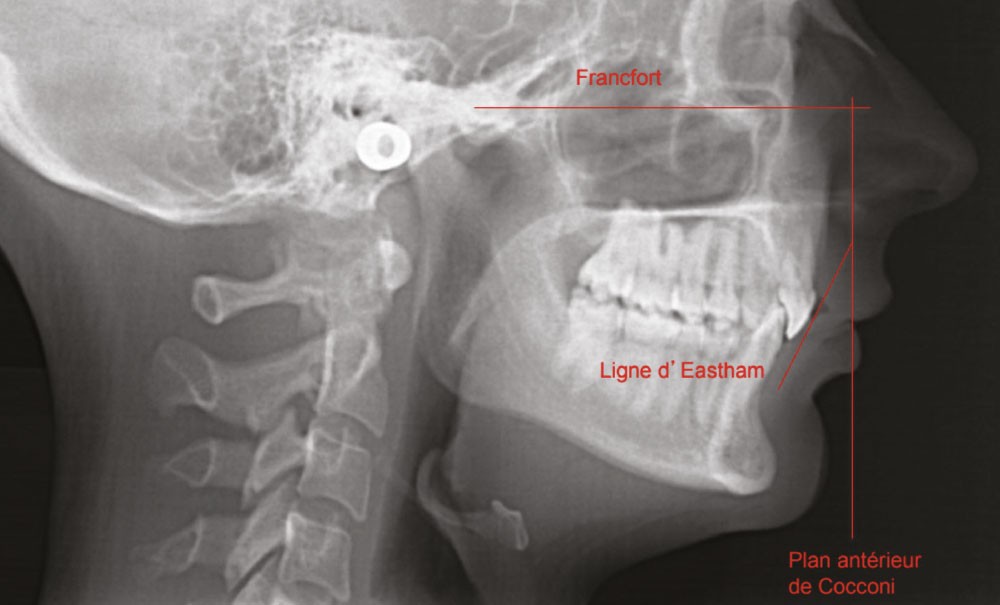

La céphalométrie aide au diagnostic. De manière simplifiée, sur une téléradiographie de profil, le plan de Francfort puis le plan antérieur de Cocconi, qui passe par le point le plus antérieur de l’os maxillaire, sont tracés ; la ligne qui passe par la face vestibulaire de l’incisive centrale maxillaire doit être tangente à ce plan (fig. 1). L’incisive centrale mandibulaire doit être au contact de son antagoniste. Si, à la suite de la simulation de cette analyse, l’incisive du bas est en dehors de l’enveloppe osseuse, cela implique le choix thérapeutique d’une chirurgie orthognatique du maxillaire et/ou de la mandibule (fig. 2).